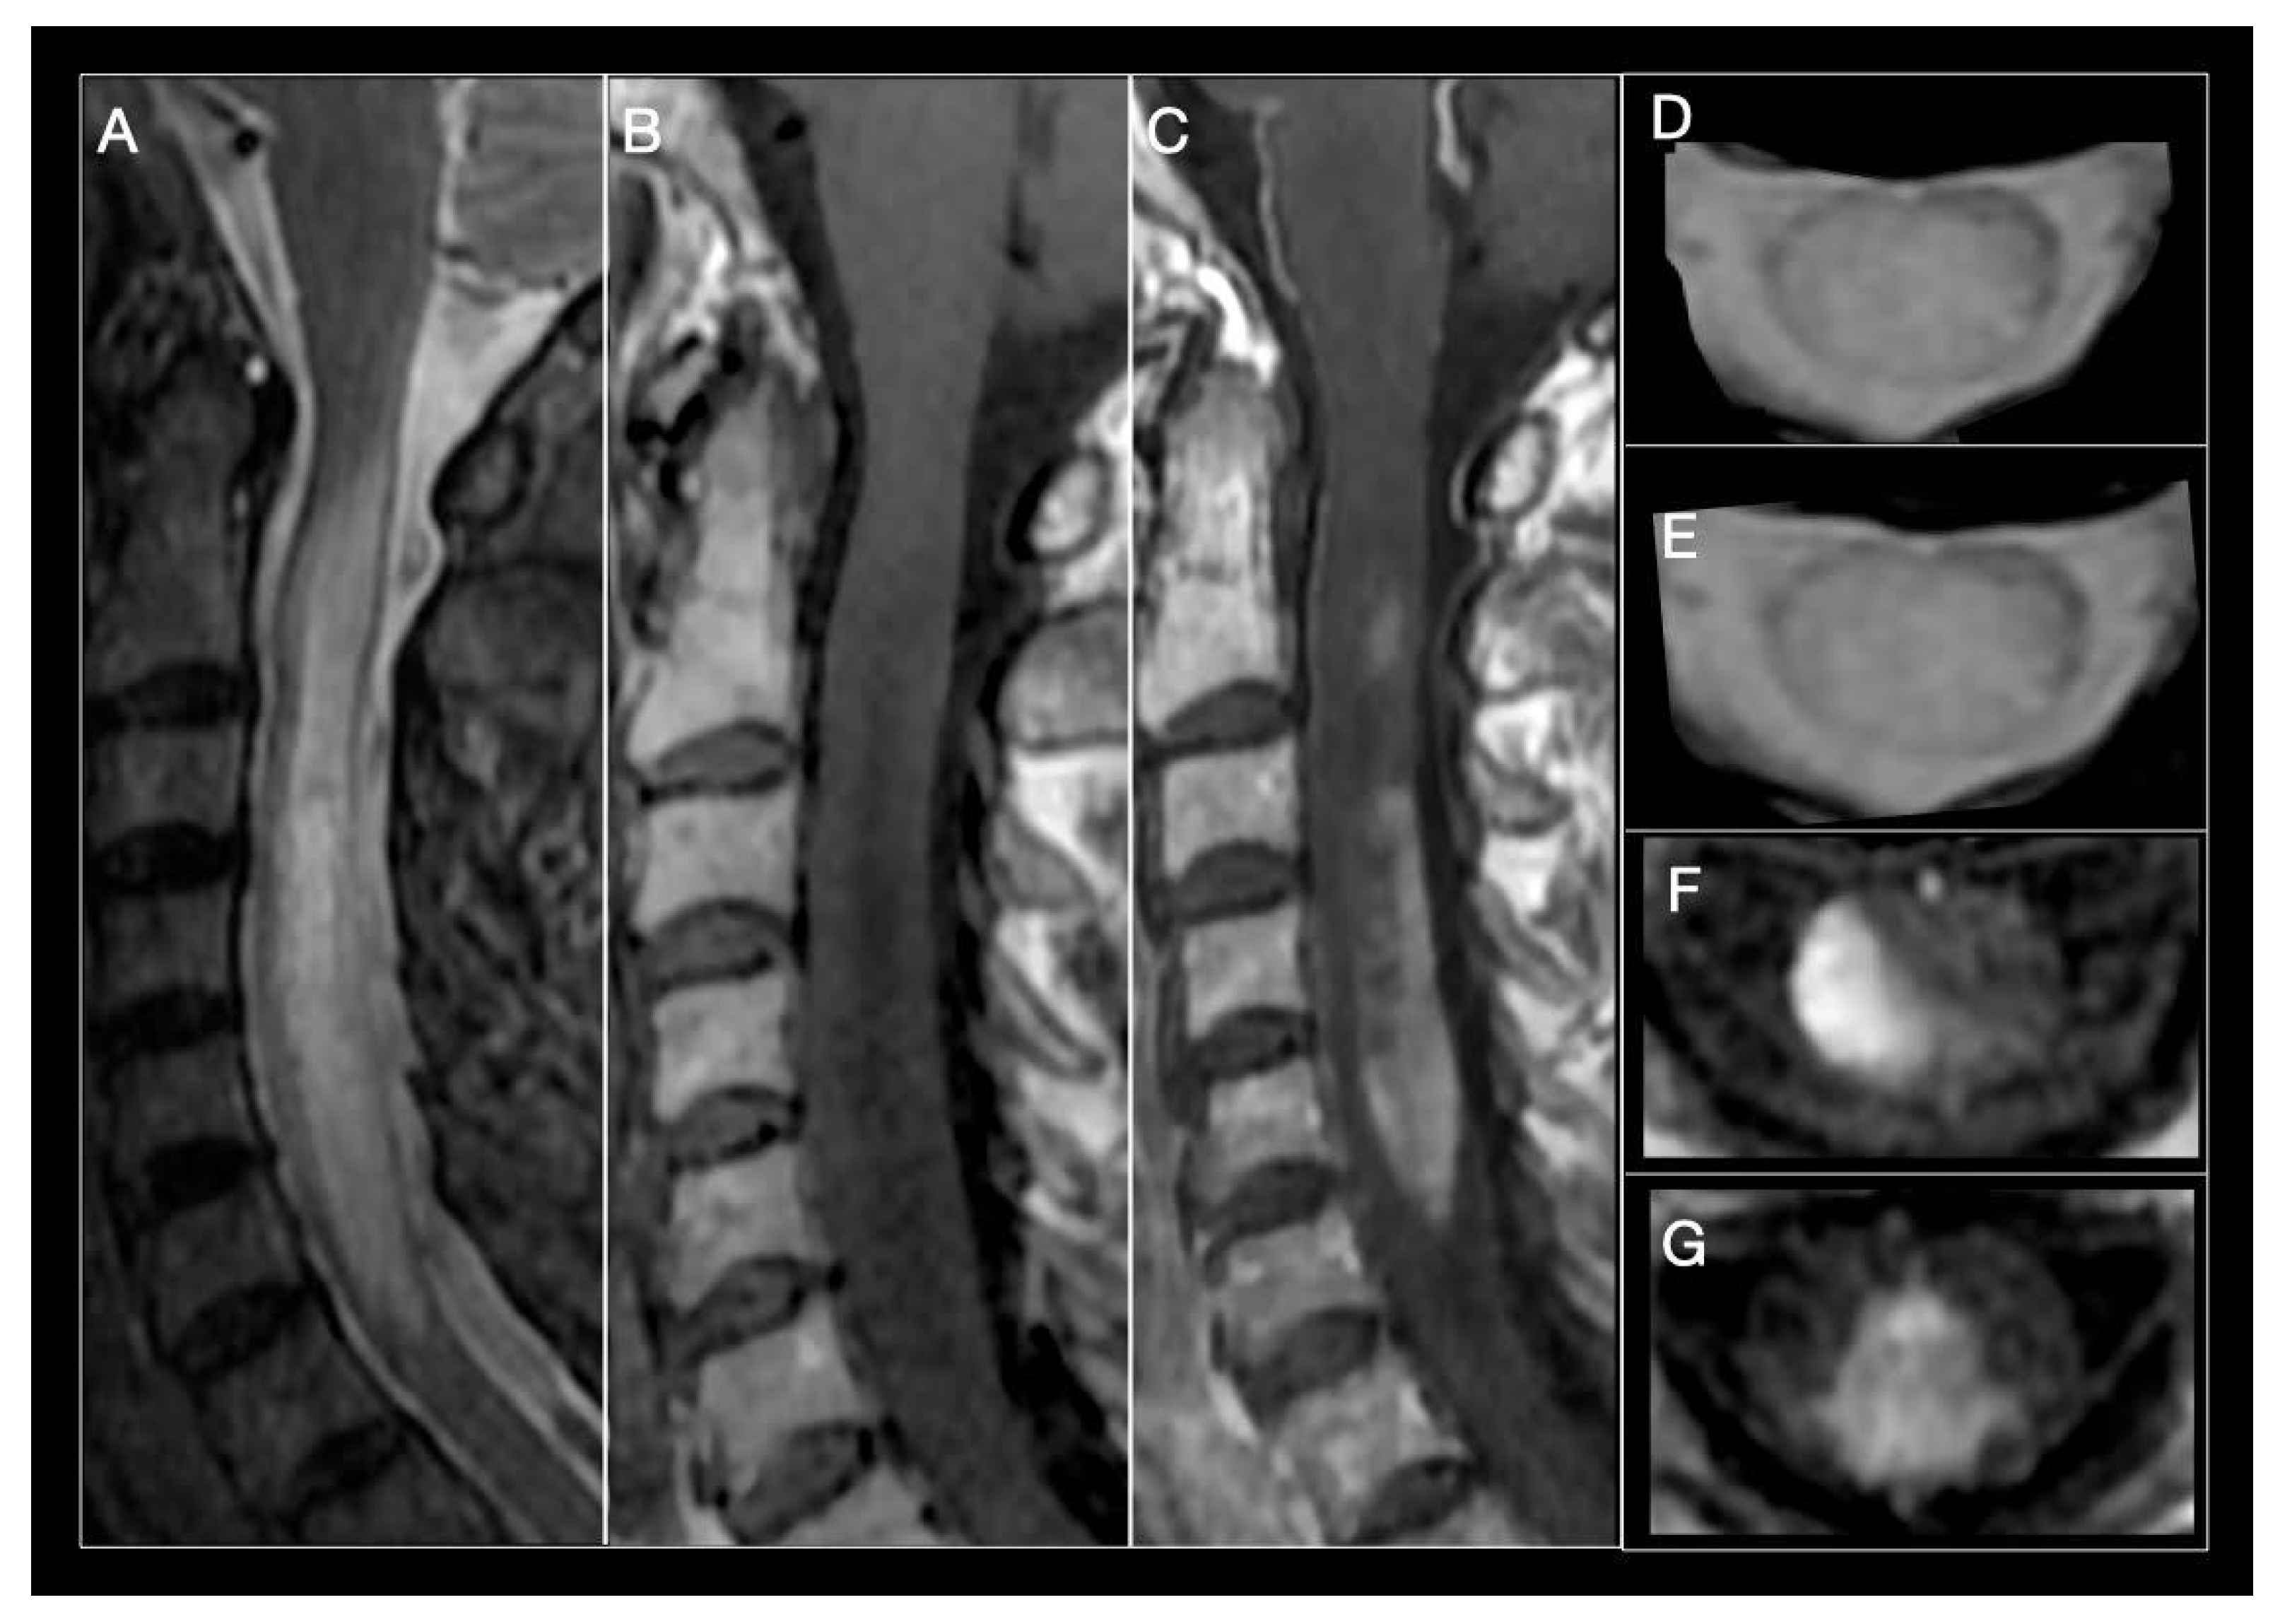

Figure 2.

Neuromyelitis optica (NMO) myelitis. Images from a 58-year-old woman with acute longitudinally extensive myelitis (C1–C7). (A) Sagittal STIR showing an extensive lesion, involving more than 3 segments, that widens the cervical spinal cord. (B) Sagittal T1-weighted sequences show an extensive T1-hypointense lesion. (C) T1-weighted images after contrast administration, extensive enhancement of cervical lesion. (D,E) Axial T2-MERGE hyperintense area that involves more than half the diameter of the spinal cord. (E,F) Axial T1-weighted, intense contrast enhancement of lateral (E) and central-posterior (F,G) areas.

Acute transverse myelitis symptoms in NMOSD patients (motor, sensitive, and frequently sphincter) are usually severe and bilateral, and recovery is incomplete compared to MS. Although overlap of clinical characteristics in MS and NMOSD myelitis does occur, symptom magnitude and disease history frequently contribute to establish differential diagnosis [30,32,120], as do certain MRI findings. LETM is the most specific neuroimaging characteristic found in NMOSD, and is uncommon in MS (Figure 2) [108]. Mirroring severe underlying tissue damage, lesions are generally hyperintense on T2-weighted, and hypointense on T1-weighted sequences [30]. Extending over three or more complete vertebral segments, they tend to localize in the center of the cord, because of the abundant AQP4 channel expression in grey matter. Lesions will usually occupy over 50% of the cross-sectional surface area of the spine, representing a complete, rather than incomplete, form of transverse myelitis which is more characteristic in MS. However, they also may be lateral, anterior, or posterior over the length of the lesion and be accompanied by cord swelling. The latter, when present, can generate concern over presence of a spinal cord tumor [123]. Chronic necrosis caused by NMOSD can in some cases result in spinal cord cavitation and cystic myelomalacia. Small areas of strong hyperintensity, higher than that of the surrounding cerebrospinal fluid (CSF), so-called bright spotty lesions, may be observed and could be useful to distinguish NMOSD from MS [124]. Acute NMO lesions extensively enhance following IV gadolinium administration. Lens-shaped ring-enhancement is detected in up to 32% of NMOSD patients [29,125,126]. Rostral extension of cervical lesions to the area postrema is another characteristic of NMOSD and can be helpful to distinguish it from other causes of longitudinal extensive myelopathy such as sarcoidosis, spondylotic myelopathy with enhancement, dural arteriovenous fistula, spinal cord infarct, and paraneoplastic myelopathy [127]. Although LETM is the most frequent form, 7–14% of NMO-myelitis involve <3 vertebral segments. However, short forms of NMO-myelitis are followed by LETM in ninety percent of cases. Short cord lesions should be suspected in patients with tonic spasm, coexistence of autoimmune disease, grey matter involvement and absence of OCB. As in MS, in 7–14% of cases, variation in presentation will be linked to time at which MRI scans are obtained [128,129,130]. Lesions limited to less than three segments will be detected at the beginning of disease or during remission [131]. In contrast, patients with longstanding disease may present short but coalescing lesions suggesting a LETM pattern [22]. Presence of a longitudinally extensive segment of cord atrophy is another characteristic finding in support of prior NMOSD myelitis [131].